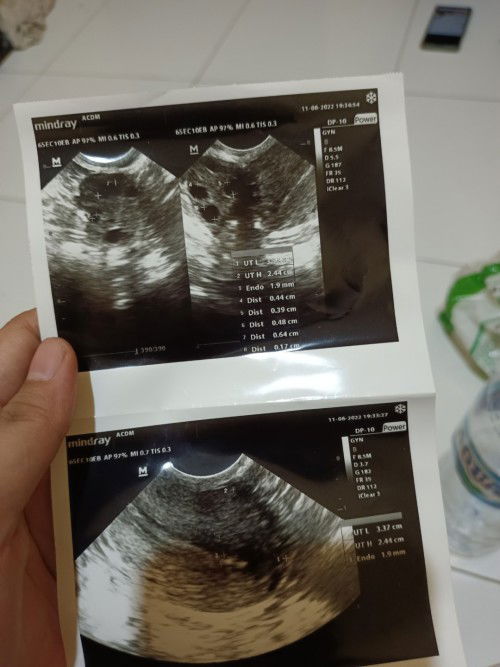

Hallo bunda ada yg sama Kya aku ga yaa haidnya ga teratur, trus kemarin 2minggu yg lalu ngrsain perut bawah keram, pingang skit, PD jga sakit, perut kembung kaya orang msuk angin, tespek garisnya 2 samar smpe 4x abis itu tes lgi hasilnya negatif dan coba USG hasilnya gaada tanda² kehamilan bahkan dinding rahim aku tipis, dan sel telurnya ukrnannya kecil 5mm ada yang sama ya Bun jdi kepikirann#seriusnanya #seriusnanya #firstmom #firstmom #firstmom #firstmom #firstmom #ingintahu #ingintahu #bantusharing #bantusharing #bantusharing #bantusharing #bantusharing #pleasehelp #pleasehelp #pleasehelp #pleasehelp #pleasehelp #firstbaby #firstbaby